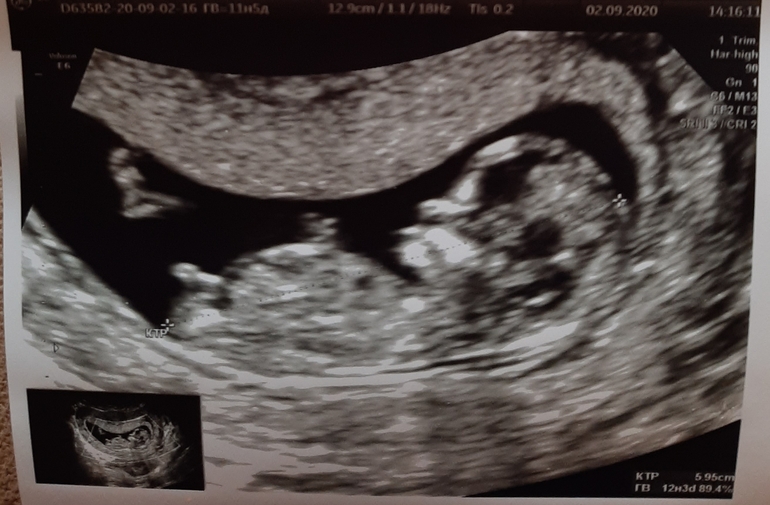

Давайте погадаем: девочка или мальчик?

Пол малышаДевочки, просто ради интереса проверим свои экспертные способности 🤓 Пол будет известен на втором скрининге, сейчас узист не сделала никаких предположений, сказала что пограничное состояние между девочкой и мальчиком, а я по половому бугорку предположила девочку))

Спасибо) Я была на узи в 14 недель из-за проблем, предположили мальчика, на следующей неделе будет второй скрининг) Я так поняла у девочек половой бугорок должен быть прямо опущен вниз, а здесь если приглядеться есть небольшая приподнятость вверх, когда было больше недель половой бугорок еще больше стал приподнят. В общем посмотрим что скажут на скрининге)

Ну вот у вас точно девочка, если сравнивать по моему фото из интернета! 😁👍

Если я правильно вижу, то что надо, то бугорок девчачий, прям как по книжному😁

Женя, а что тут видите?